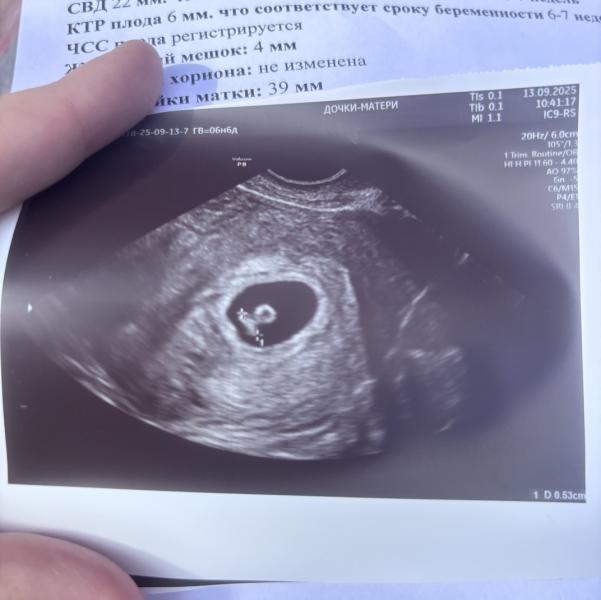

Первое УЗИ при беременности: срок по месячным и размер эмбриона

Приветики🥰Была на первом узи,сердечко бьется , по месячным срок 6,6 ,а эмбриончик 6,3) мой малыш похож на печать🤣или осьминога